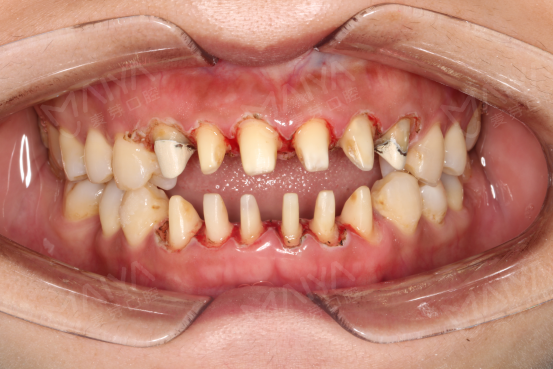

34岁的董女士是深圳市一家食品店的老板,由于自身工作的原因,董女士的牙齿很早便出现了问题,10年前就为自己的上下前牙做了金属烤瓷修复,但是由于平时自己疏于护理,最近牙齿牙龈发黑,为了在客户面前展现最美的笑容,董女士多方了解最终来到了麦芽口腔。

治疗前的董女士

修复前的牙齿

接待董女士的是麦芽口腔的修复学专家熊少军专家,熊医生在得知董女士的情况后,详细地为她做了口腔检查。